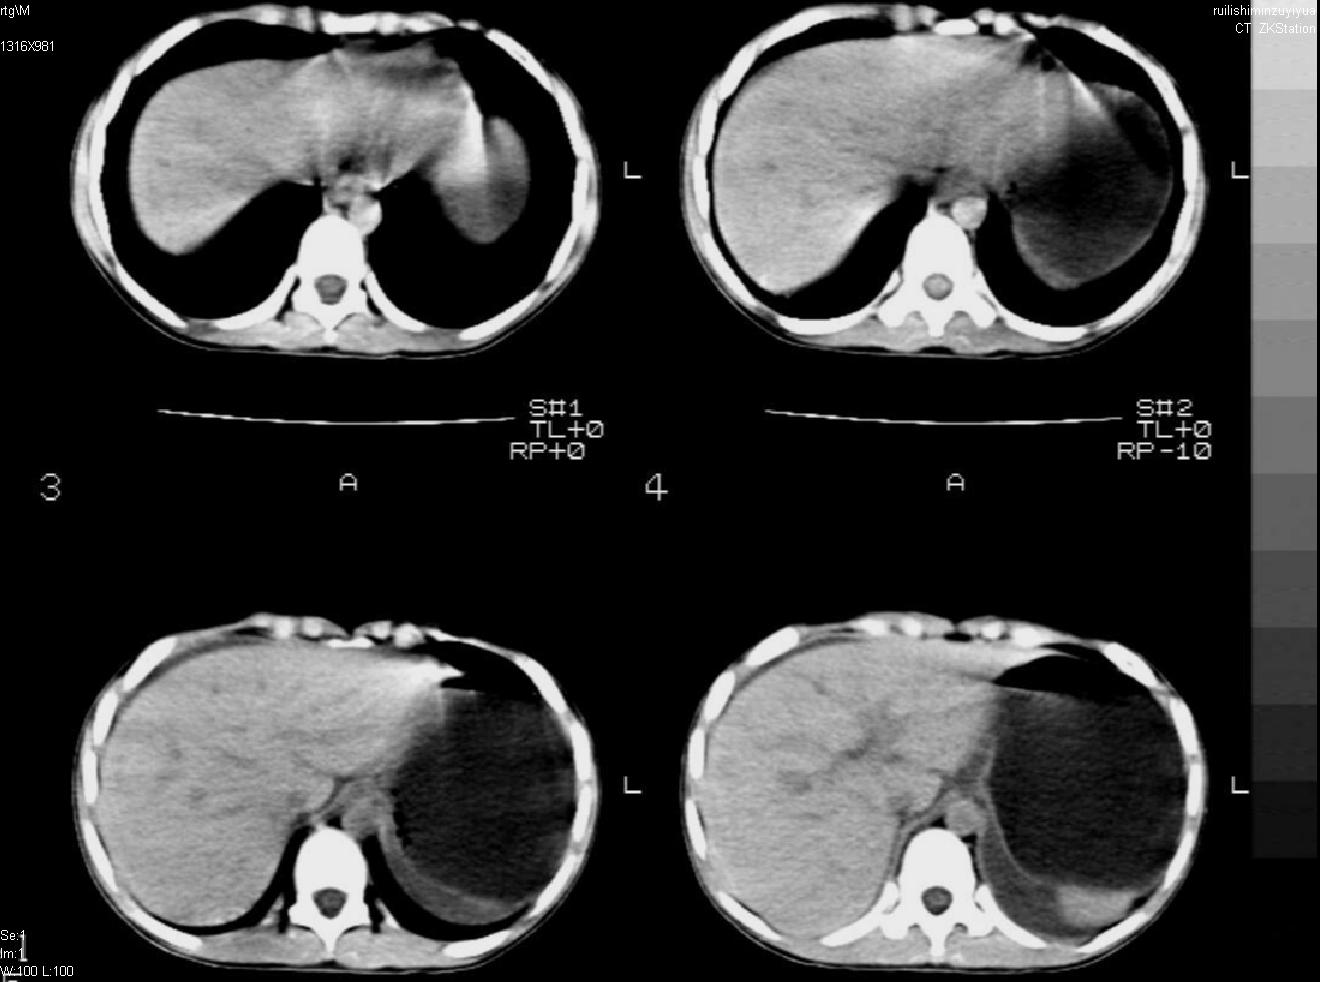

标题: PED0282:女,10岁,上腹疼痛2周 [打印本页]

标题: PED0282:女,10岁,上腹疼痛2周

b超:胆囊结石。疑坏死性胰腺炎

急性胰腺炎

考虑急性胰腺炎,胆道寄生虫。

考虑急性胰腺炎,

考虑急性胰腺炎

支持小儿急性坏死性胰腺炎。